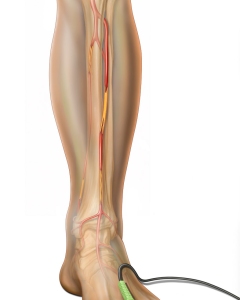

Internal Art Medical Illustration

Blending Art, Anatomy and Science for Creative Visuals

Patient & Professional Marketing

Welcome to my Patient and Professional Marketing page, where I harness the power of anatomical illustrations to educate and empower both patients and medical professionals. My unique approach combines artistry and education to convey complex surgical procedures and the utilization of medical devices in an easily understandable manner.